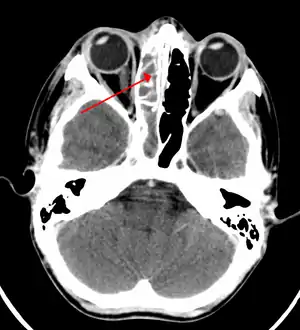

| A CT scan showing sinusitis of the ethmoid sinus | |

For sinusitis lasting more than 12 weeks, a CT scan is recommended.[53] On a CT scan, acute sinus secretions have a radiodensity of 10 to 25 Hounsfield units (HU), but in a more chronic state they become more viscous, with a radiodensity of 30 to 60 HU.[55]